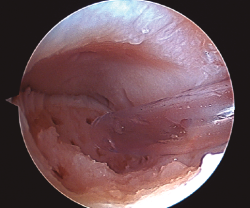

Figura 2. Técnica de estimulación medular con nanofracturas. Obsérvense los bordes del curetaje y la cruentación de la capa mineralizada.

- Posteriormente, realizamos la técnica de estimulación seleccionada entre: brocado o microperforaciones o nanoperforaciones. Preferimos realizar estas últimas a perforaciones más grandes que pueden dañar el hueso subcondral u otras técnicas de brocado con agujas de Kirschner que pueden producir necrosis inducida por el efecto térmico (Figura 2). Cada “nanofractura” debe realizarse separada 3-4 mm con una profundidad de 9-10 mm y un diámetro de 1 mm.